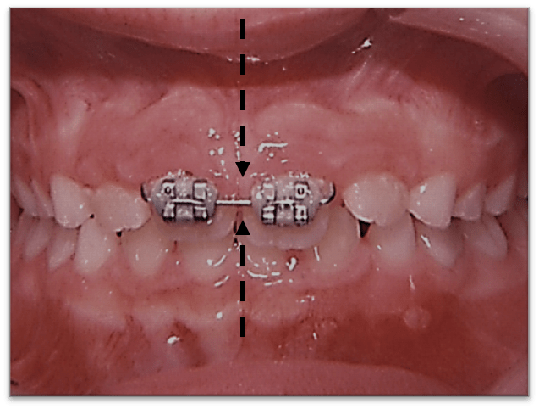

When the maxilla is properly developed bilaterally, the condyle is free to regain its correct position on the disk. As this occurs the deviation of the mandible return to normal. Proper diagnosis and treatment will result in long term stability.